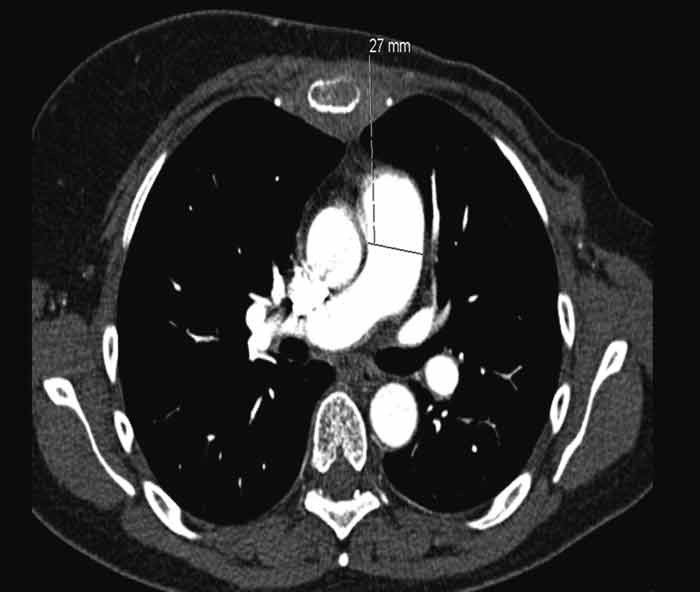

CT thorax on the 16th day from admission showed a further expanded truncus pulmonalis, 37 mm (fig. 2) and newly developed scattered, consolidating opacities in the upper lobe of the left lung. Compared with previous ECGs, a new ECG showed findings as with right-side strain and a QR pattern in V₁, negative T in V₂ and pronounced R-loss in the anterior wall leads. The patient was referred for echocardiography, which was planned for the next day. From the same day she had increasing tachycardia and hypotension and after a while was transferred to the Pulmonary Ward's observation department for BiPAP respiratory support. On the morning of the 18th day since admission (about ten weeks after the very first hospitalisation for dyspnoea) the patient suddenly suffered respiratory arrest and was unresponsive. Advanced heart-lung resuscitation was initiated, but it was not possible to re-establish independent circulation. The patient was declared dead about 30 minutes after the start of resuscitation.

Figure 2  Volume CT thorax with intravenous contrast taken during last hospitalisations shows pronounced truncus pulmonalis…

Figure 2 Volume CT thorax with intravenous contrast taken during last hospitalisations shows pronounced truncus pulmonalis with diameter 37 mm causing suspicion of pulmonary hypertension